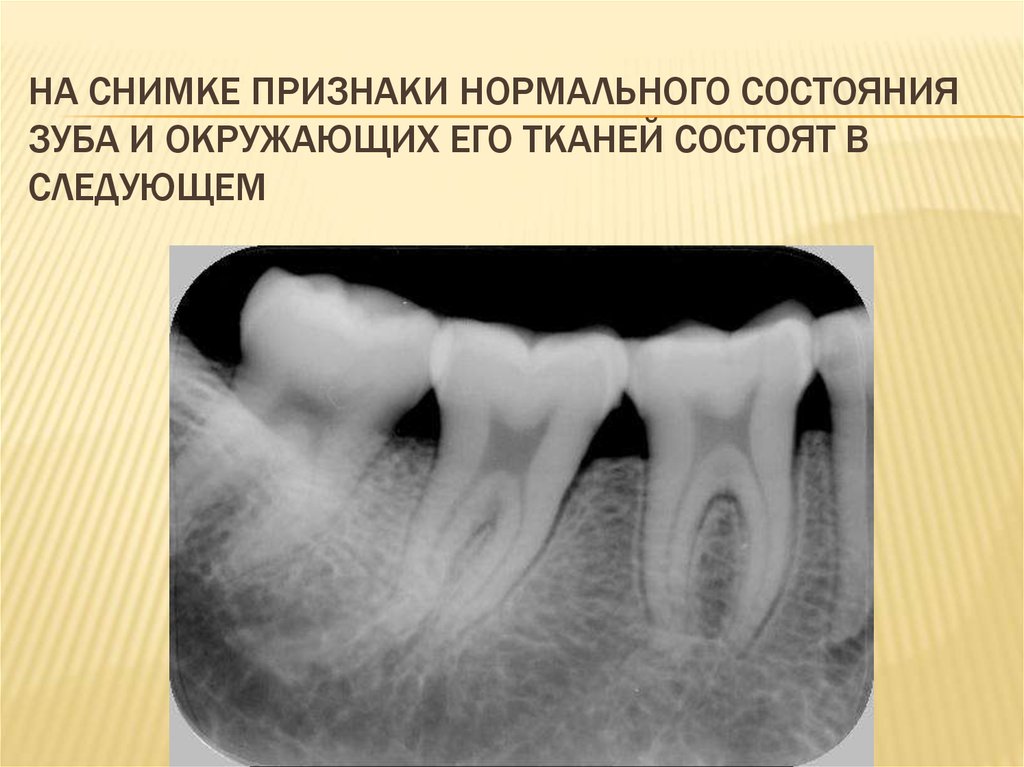

НА СНИМКЕ ПРИЗНАКИ НОРМАЛЬНОГО СОСТОЯНИЯ

ЗУБА И ОКРУЖАЮЩИХ ЕГО ТКАНЕЙ СОСТОЯТ В

СЛЕДУЮЩЕМ